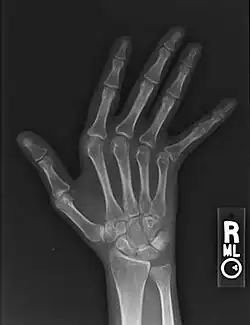

Jaccoud arthropathy seen on a hand x-ray. As opposed to arthropathy due to rheumatoid arthritis, there are no erosions.

Jaccoud arthropathy (JA), is a chronic non-erosive reversible joint disorder that may occur after repeated bouts of arthritis.[1][2] It is caused by inflammation of the joint capsule and subsequent fibrotic retraction, causing ulnar deviation of the fingers, through metacarpophalangeal joint (MCP) subluxation,[1][3] primarily of the ring and little-finger.[3] Joints in the feet, knees and shoulders may also get affected.[1] It is commonly associated with systemic lupus erythematosus (SLE), and occurs in roughly 5% of all cases.[1][2]

Plain hand radiographs typically show marked ulnar subluxation and deviation at the metacarpophalangeal joints. Absence of erosions is a notable feature, although occasionally "hook" erosions may be observed, which are similar to those seen in SLE and ankylosing spondylitis. Evidence of muscle (soft tissue) atrophy also may be present.